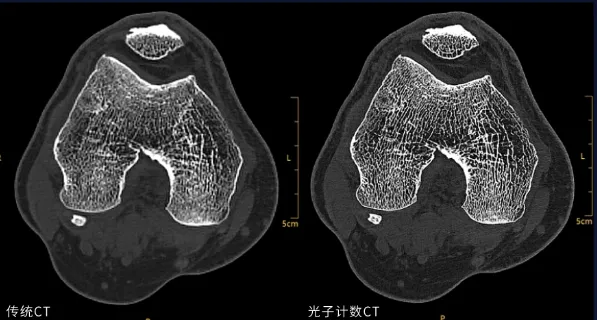

与普通CT相比,1024层CT就像用超细网格扫描身体,能够捕捉到更细微的变化。它整合了16cm宽体覆盖、0.3125mm超薄层厚与46.5lp/cm超高空间分辨率三大核心优势。

0.3125mm的超薄层厚成像能力,可清晰呈现内耳、口腔、骨小梁等以往难以捕捉的精细解剖结构,让早期微细病变无所遁形。这相当于头发丝直径的几分之一。